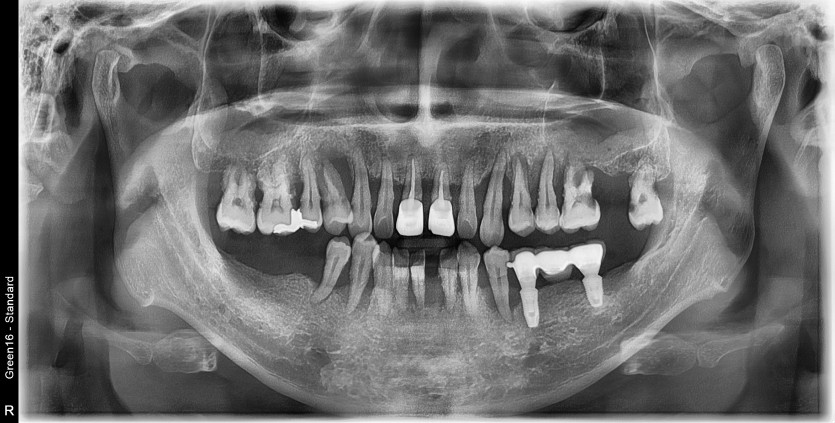

만 41세 전체 임플란트 증례

전체 임플란트 증례입니다.